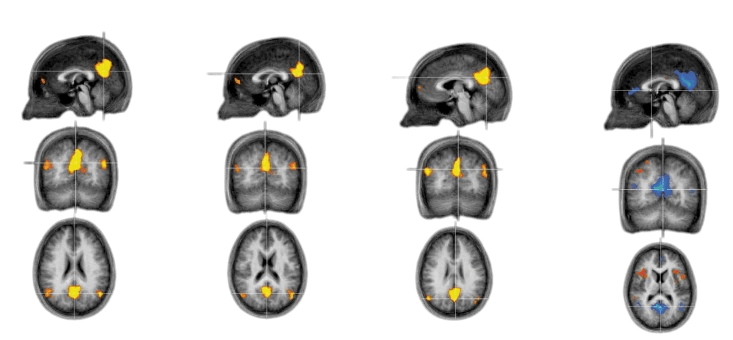

Resting State Boredom Sustained Attention Interest (Modified from Danckert and Merrifeld 2016)

“Regions of the posterior DMN consistently active in the resting state, boredom mood induction and sustained attention task are highlighted. The same regions were anticorrelated during the interest mood induction (see, Tables for full details). Clusters shown in warm colours reflected correlated activity, whereas clusters shown in cool colours represent anticorrelated activity” [2]

The default mode network (DMN) consists of mainly the medial prefrontal cortex, posterior cingulate cortex, and the inferior parietal lobule. The precuneus and middle temporal lobule are sometimes considered the DMN. Activation of this region during boredom, resting state, and sustained attention is “anticorrelated” with regions highlighted in blue during interest-engaging activities. These findings imply a tradeoff between engaging, high intensity activities and imaginative, creative brainstorming associated with the DMN. Thus, it is important to schedule set time periods during the day to brainstorm and create.